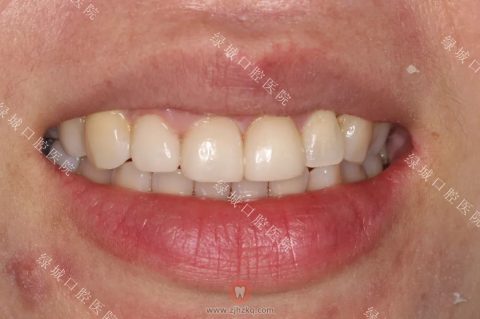

这是一个门牙畸形的患者,因为大门牙关系到一个人的整体形象,为了美观做了全瓷贴面,效果还是很棒的。

通过全瓷贴面治疗,牙齿变白且美观了